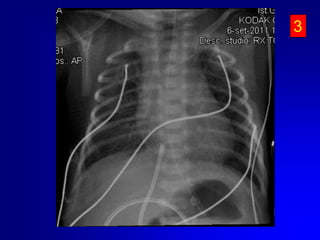

Eseguire sempre controllo radiografico o ecografico della posizione del catetere..

Cateterismo vena ombelicale - ComplicazioniInfezioniTromboemboliche. Se gli emboli sono infetti potranno causare numerosi ascessi. Catetere malposizionato nel cuore o nei vasi. Versamento pericardico/tamponamento cardiaco (perforazione cardiaca) Aritmie cardiacheCatetere malposizionato nel sistema portaleNECNecrosi epatica (trombosi delle vene epatiche o infusionedi soluzione ipertonica o vasospastivca nel tessuto epatico. Cisti epatiche

Eseguire semprecontrollo radiografico o ecografico della posizione del catetere..

Cateterismo vena ombelicale- ComplicazioniInfezioniTromboemboliche. Se gli emboli sono infetti potranno causare numerosi ascessi. Catetere malposizionato nel cuore o nei vasi. Versamento pericardico/tamponamento cardiaco (perforazione cardiaca) Aritmie cardiacheCatetere malposizionato nel sistema portaleNECNecrosi epatica (trombosi delle vene epatiche o infusionedi soluzione ipertonica o vasospastivca nel tessuto epatico. Cisti epatiche